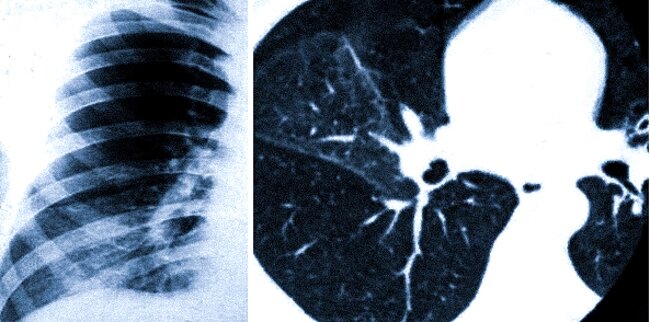

СКТ в выявлении осложнений пневмонии

Пневмония опасна не столько самим воспалением, сколько осложнениями, которые она может вызвать. СКТ играет решающую роль в их своевременном обнаружении. Клинические рекомендации подчеркивают, что при подозрении на осложнения показания к проведению компьютерной томографии должны быть расширены. Среди наиболее частых и опасных осложнений выделяют:

Абсцесс легкого: Это ограниченное гнойное расплавление легочной ткани, формирующее полость. На снимках КТ абсцесс виден как полость с толстыми стенками и уровнем жидкости (гноя). Своевременная диагностика позволяет избежать прорыва абсцесса в плевру или сепсиса.

Парапневмонический плеврит и эмпиема плевры: Воспаление может перейти на плевру (оболочку, покрывающую легкие), вызывая скопление жидкости в плевральной полости. КТ четко показывает даже небольшое количество выпота, а при эмпиеме (гнойном плеврите) визуализируются утолщенная плевра и характерное содержимое.

Септическая эмболия: Инфекционные тромбы могут заноситься в легкие из других очагов воспаления, вызывая множественные мелкие очаги некроза. КТ позволяет обнаружить эти очаги, часто расположенные по периферии легких.

Фиброзные изменения: После перенесенной пневмонии, особенно тяжелой, на месте воспаления может разрастаться рубцовая соединительная ткань. Это состояние называется пневмофиброзом и приводит к необратимому снижению эластичности легких и дыхательной недостаточности. КТ — единственный метод, позволяющий достоверно оценить степень поствоспалительных фиброзных изменений.

Таким образом, СКТ помогает не только на этапе диагностики, но и в динамике, позволяя оценить эффективность лечения и выявить остаточные явления, требующие реабилитации.